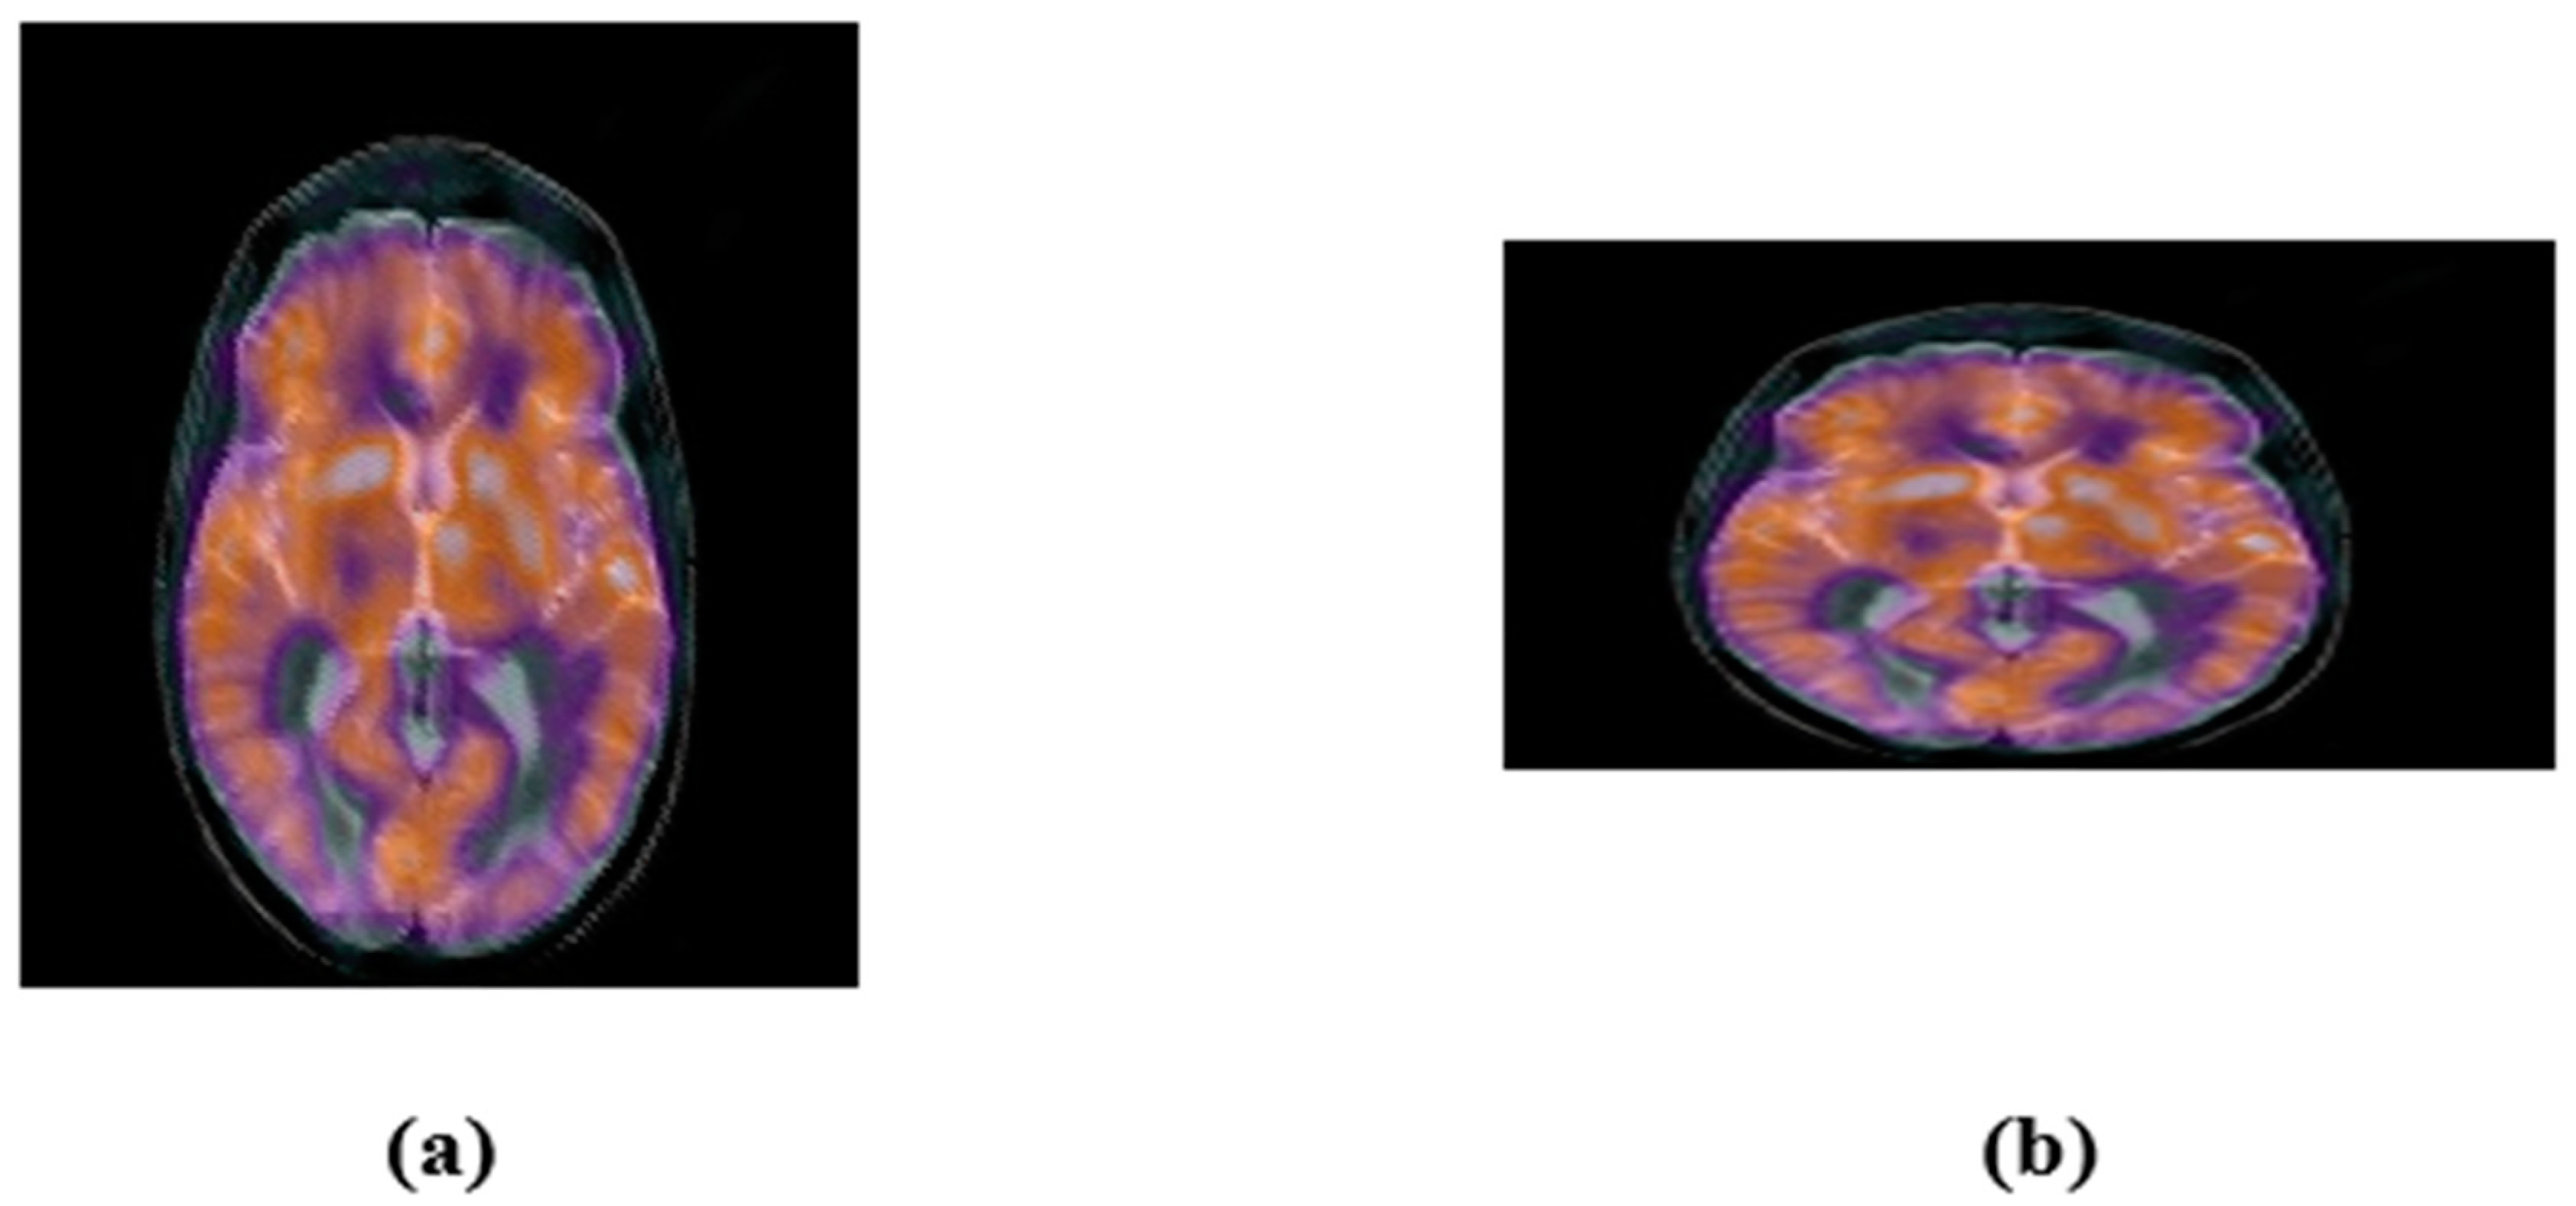

2.3. Accurate Computation of New Multi-Channel Gaussian-Hermite Moments of Color Images

3. Proposed Zero-Watermarking Algorithm